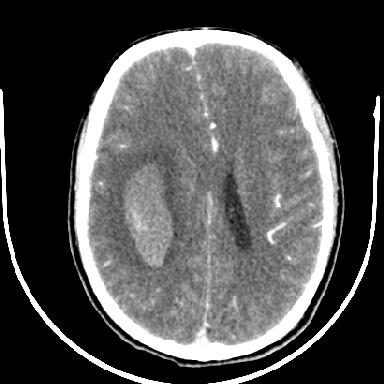

标题: CT6056:脑出血(血管畸形?) [打印本页]

标题: CT6056:脑出血(血管畸形?)

m 40突发头痛左侧偏瘫3小时

考虑高血压性脑出血,依据:

1是高血压性脑出血的好发部位,形态呈肾形,是高血压性脑出血的常见形状

2增强时占位效应加重了,考虑出血还没有停止

3病灶周围水肿不是太厉害,一般肿瘤出血水肿多非常明显

4病灶周围的‘软组织’影没有明显的强化

5至于脑血管畸形引起的出血,暂时没有看到明显的畸形血管影,也不太支持

支持右侧基底节脑出血

右侧基底节区脑出血.

支持右侧基底节区(主要为外囊区)原发性脑出血。

另附部分资料:“血液溢出血管外形成血肿,其内含有大量血红蛋白、血浆白蛋白,球蛋白,因这些蛋白对x线的吸收系数高于脑质,故ct呈现高密度阴影,ct值达40~90h,最初高密度灶呈非均匀一致性,中心密度更高,新鲜出血灶边缘不清。基底节区血肿多为“肾”型,内侧凹陷,外侧膨隆,因外侧裂阻力较小,故向外凸,其它部位血肿多呈尖圆形或不规则形”

术中抽出40ml陈旧血液,血肿底部似见一条索血管影